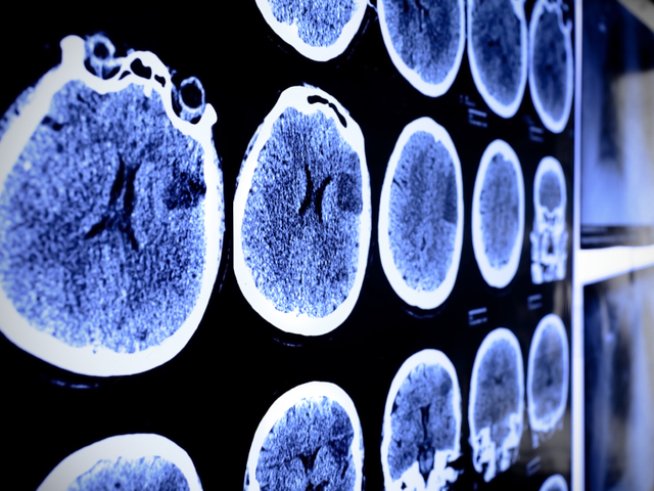

Знаете ли, че инсултът подсказва за себе си не само с класическите симптоми на състоянието? Инсултът е остро нарушение на кръвообращението в мозъка. Нещо повече, заболяването засяга както двата пола, така и хора в по-млада възраст.

Много е важно да сте добре запознати със симптомите на инсулта, за да можете да реагирате още в първите минути. Ако инсултът е в лявата част на мозъка, тогава дясната страна на тялото е засегната. Това често води до скованост, изтръпване и други.

Ако дясната страна на мозъка е поразена от инсулт, лявата страна на тялото е засегната. Ударът в задната част на мозъка може да повлияе на зрението, докато в предната част може да повлияе на речта.